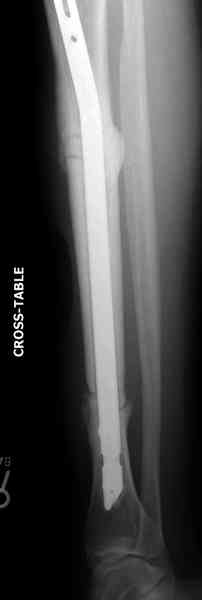

Нет. Просвет внутри кейджа - 13 мм, штифт - 12 мм. Не так там и много пространства то есть. Но вопрос правильный, интересный, из разряда современных нерешенных проблем.

Недавно на нашей ежемесячной Morbidity&Mortality

conference мы разбирали похожий случай, ложный сустав большеберцовой кости после резекции опухоли.

К нашему онкологу-ортопеду обратился больной с жалобами на боли в голени, из рассказа - год назад была сделана биопсия большеберцовой кости, но название заболевания "не запомнил”.

Оперирован в военном госпитале с заменой сегмента

аллокостью большеберцовой кости и после демобилизации явился для постоянного наблюдения по месту жительства.

Наши имели проблему со сращением, пришлось им сделать динамизацию, дополнительную аутопластику.

Снимки представлены.

Не оригинальное, подход не раз был демонстрирован нас в стране проф. Анатолием Федоровичем Лазаревым (ЦИТО), который это называет "металлокаркасная пластика". У нас в институте в другом отделении он

помогал сделать несколько таких металлокаркасов, только, насколько я помню, без блокируемых стержней. А в мире эта методика довольно давно

применяется, хотя и не массово. Например, осенью прошлого года на конференции общества Кюнчера в Страсбурге было хорошее сообщение на эту тему. 17 больных, результаты уже до 5 лет.

The cages are commercially available but up to 10 cm. So we measured the needed length on x-rays, added 2 cm at both ends for sure that

the resected piece will include all, and resulted with 15 cm which one was ordered and individually made by the same factory. So yes, we made the gap to fit the cage.

The inner diameter of the tube is 13 mm, the nail was 12 mm, so not so much space to put something inside. Yes, this is really shaft endoprosthesis which i hardly ever would offer for a young football player. Though... Maybe we would when we collect some experience with this sort of implants to feel/prognose its strength in different settings.